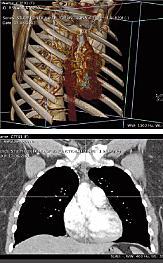

Er du – eller din sekretær – træt af at skulle gå på telefonjagt efter en kollega på et andet hospital og bede vedkommende fiske f.eks. et røntgenbillede frem på en patient?Er du træt af at vente rigtig længe på at få overført f.eks. en CT-skanning, når den endelig er fundet?Er din patient ked af at skulle gennem en helt ny røntgenoptagelse, eller hvad det nu kan være, fordi den gamle optagelse netop ikke kan findes?I så fald er der hjælp på vej.I denne uge starter et projekt, der fundamentalt vil ændre den måde, sundhedsbilleder i bred forstand - alt fra skanninger og røntgen over EKGer til bronkoskopier mm – håndteres på i Danmark .”I dag bruger man forfærdeligt lang tid på at finde billeder frem. Hvis man så ikke kan finde dem, så tages billederne igen. Det er skidt for patienten, som skal bruge tid på det og måske bliver udsat for unødvendig stråling. Og det er skidt for finanserne”, siger konsulent Henrik Hvolris fra it-udviklingsafdelingen i Region Sjælland, som er den region, der holder tov i projektet.Det tager tid og ressourcer at rekvirere og overføre billeder og beskrivelser fra en radiologisk afdelings systemer til en andens, og hvis det ikke umiddelbart flasker sig, så tages der nye billeder.”Alene i Region Sjælland har vi 10-12.000 retakes, som finder sted, fordi et eller andet billede ikke kan findes. De koster vel omkring 1.000 kroner hver, så det er 10-12 mio. kroner om året”, fortæller han.De fem regioner har regnet ud, at en smartere billedhåndtering kan spare omkring 50 mio. kroner om året i alt.Som Henrik Hvolris udtrykker det, så er det ”mere end nok til at betale for dette her system".Det, regionernes it-samarbejde, RSI, har skabt, er et billedindeks – en indholdsfortegnelse, en database, et register, eller hvad man nu vil kalde det - hvorfra læger selv på deres egen pc vil kunne hente eksisterende billedmateriale og beskrivelser frem, selv om undersøgelserne ligger fordelt på flere forskellige RIS/PACS systemer.Fordi billedfilen ikke skal transmitteres et eller andet sted fra og downloades til deres pc men populært sagt kan ses i cyberspace, kan undersøgelsen kaldes op på et splitsekund.Projektet er kernen i det interregionale samarbejde om billedindekset, der har som mål – eller pejlemærke, som RSI kalder det – at billeder skal kunne udveksles mellem samtlige sygehuse med udgangen af 2012.Ud over at give adgang til den enkelte patients billedmateriale, viser billedindekset også en kronologisk oversigt over den enkelte patients undersøgelser.Henrik Hvolris demonstrerer systemet ved at kalde en omfangsrig mave CT-skanning op på sin skærm – den består af 742 billeder. Det tager 1,5 sekunder.Flere læger kan kalde det samme billede op samtidigt, så man f.eks. kan holde konferencer pr. langdistance. En øvelse, der ikke er helt ueffen, nu hvor sundhedslandskabet omkalfatres, så f.eks. højtspecialiseret kunnen samles i store centre.En ekstra bonus ved det sjællandske system er, at lægerne – ligesom billeddiagnostikerne – kan ”lege” med billederne. Vende og dreje dem – se dem tredimensionalt – zoome ind og ud osv.Skridt for skridtDet nye system indføres ikke på en gang – det ville også være umuligt.”Vi starter med røntgenbillederne, og så kommer de almindelige billeder og EKG”, siger Henrik Hvolris.”Det er kolossale mængder af data, der skal overføres til det nye billedindeks, og vi starter med det nyeste først”, siger han.Til maj starter så den nationale udrulning, og region Nordjylland er umiddelbart bedst placeret til at blive den næste region, som indfører systemet.Farvel til fax og CDSystemet går nu fra skrivebord ud i pilotfase i virkeligheden, og lægerne venter sig meget af det.”Det er ekstremt vigtigt med tilgang til information”, siger overlæge og leder af kardiologisk ambulatorium i Roskilde, Steen Carstensen.”Hvis den information mangler, man har brug for, når man sidder over for en patient og skal beslutte, hvilken behandling man vil anbefale, så må man sende patienten hjem. Lægge alting til side, finde informationen frem, og så får man patienten tilbage igen dagen efter, hvis det går hurtigt. Så skal man sætte sig ind i det hele igen. Det er dobbeltarbejde”, siger han.Det er måske især i de tilfælde, hvor en patient krydser regionsgrænser, det nye system kan komme til at spille en stor rolle.”Det, der har været realiteten er, at et fremmed sygehus har været nødt til at faxe f.eks. EKGer til os. Så får man et stykke papir, der kun er tilgængeligt for lægen, der sidder med det".Og når Roskilde samarbejder med f.eks. Odense Universitetshospital, så foregår billedsiden stadig ved at brænde CDer med f.eks. ultralydsskanninger og fremsende dem.”Den kan blive væk, og kun lægen med CDen kan se. Det er den løsning, vi har, indtil vi forhåbentlig snart kan dele med de andre”, siger Steen Carstensen med henvisning til udrulningen af det sjællandske system til andre regioner.Bjørnen skal skydes førstForventningerne er store, men som ved ethvert stort it-system er der også er en masse ting, som kan gå galt.”Vi, der har erfaring med it systemer, ser med kritiske briller på den slags hele tiden. Vi sælger ikke skindet, før bjørnen er skudt. Vi har en lang proces foran os, men jeg tror, det kommer til at fungere”, siger ledende overlæge Carsten Sloth fra røntgenafdelingen i Næstved.”Sådan noget som dette her har været efterspurgt gennem mange år. Det er et længe næret ønske, der er ved at gå i opfyldelse".”Meget af det, der ligger foran os, er udviklingsarbejde, som vi slet ikke kender arten af endnu. Men meget af teknikken er prøvet igennem før. Der er lignende systemer, som fungerer i andre lande”, siger han.